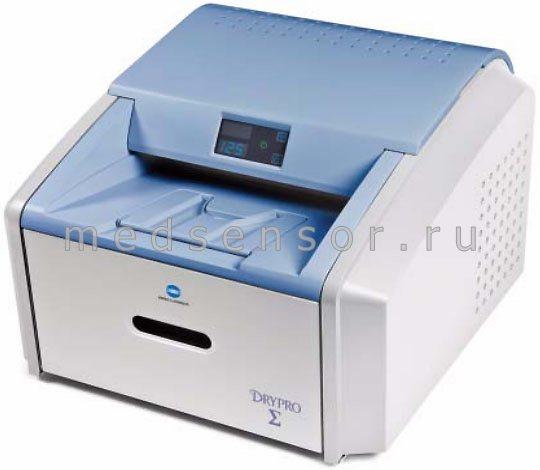

Лазерная камера для печати медицинских изображений на пленке стандарт dicom

/CMI%201000-640x500.jpg)